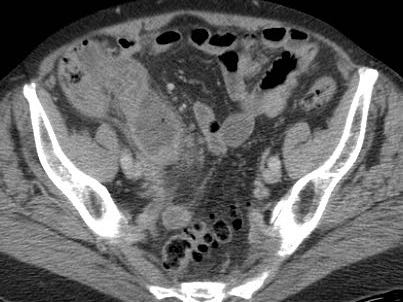

Dịch tự do

Một lượng nhỏ dịch trong phúc mạc giảm âm (*) có ít giá trị chẩn đoán và có thể gặp trong cả viêm ruột thừa cấp chưa thủng (trái) lẫn viêm ruột thừa thủng (mũi tên) (giữa), nhưng cũng có thể gặp ở bệnh nhân có ruột thừa bình thường (phải).

Lượng dịch lớn hơn, đặc biệt nếu khu trú và/hoặc đục, thường kèm theo liệt ruột khu trú hoặc toàn thể, là dấu hiệu nghi ngờ thủng.

Thông thường những bệnh nhân này có tình trạng nặng, đau nhiều và CRP tăng cao.

Ở người phụ nữ 56 tuổi này với CRP 180, siêu âm phát hiện dịch trong phúc mạc đục (*) và có thể thấy ruột thừa viêm với sỏi phân (mũi tên).

CT xác nhận hai sỏi phân ở hố chậu phải với hình ảnh khí bất thường, nghi ngờ viêm ruột thừa thủng.

Chọc hút dưới hướng dẫn siêu âm xác nhận dịch mủ.

Phẫu thuật cấp cứu phát hiện viêm ruột thừa thủng với nhiễm bẩn mủ bốn góc phần tư ổ bụng.